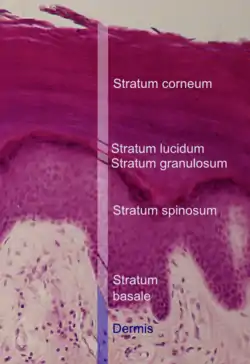

Microscopic image showing the layers of the epidermis. The stratum corneum appears more compact in this image than above because of different sample preparation. | |

Cross-section of all skin layers Illustration of epidermal layers

Illustration of epidermal layers Optical coherence tomography of fingertip